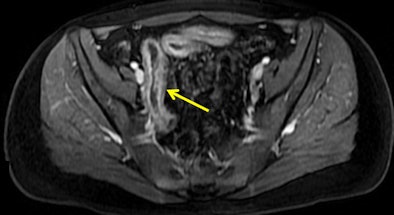

| Images show patient with terminal ileitis. CT (above) and gadolinium-enhanced MR enterography (below) show abnormal wall thickening. Both readers agreed on the interpretation of images. All images courtesy of David Grand, MD. |

![]() |